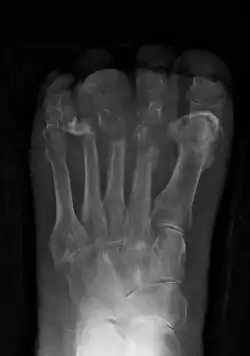

Osteomyelitis of the 1st toe | |